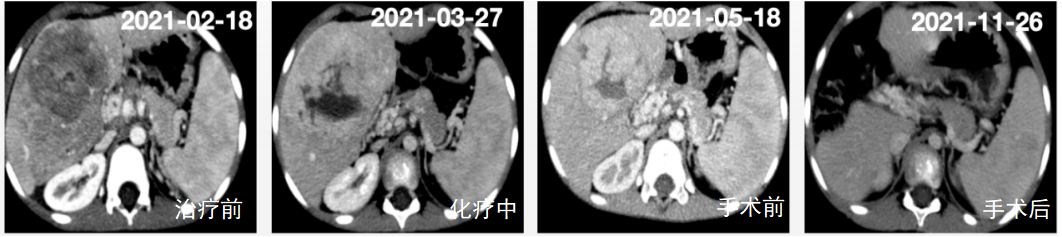

跟踪治疗前后变化,判断效果。

CT增强扫描应用于疗效评价(肝肿瘤治疗前-化疗中-手术前-手术后比较)